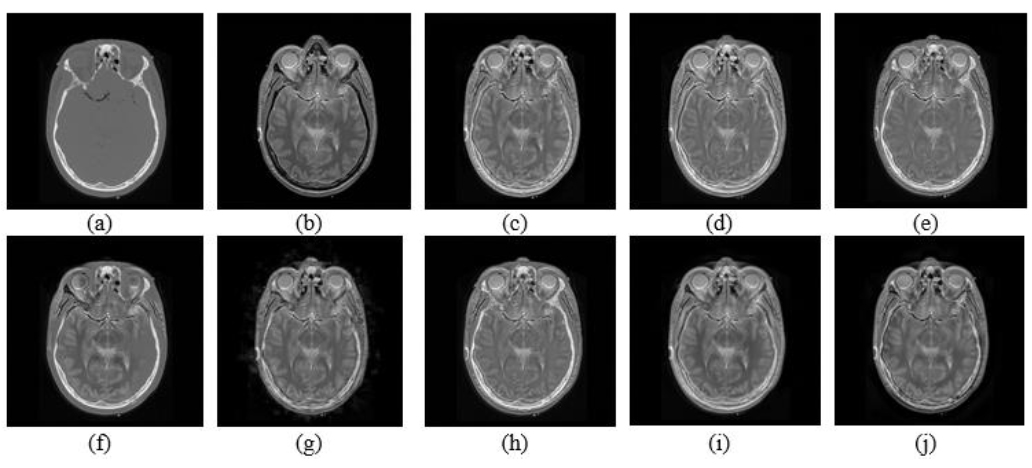

7. EXPERIMENTAL SETUP AND DISCUSSION

In this section, a comprehensive evaluation of eight multimodal medical image fusion techniques, LEGFF, FGF-XDOG, MDHU, FDO-DPGF, CSMCA, S-ADE, PCLLE-NSCT, and NSST-AGPCNN, is conducted for dataset 1 [114] utilizing diverse quantitative criteria to evaluate information content, image quality, edge preservation, and noise reduction, and has been described in Table 15 along with mean and standard deviation. Of these evaluated approaches, LEGFF exhibited the highest entropy of 6.86 and average gradient of 7.06, signifying enhanced information richness and edge definition, while the mean entropy value is 6.44 ± 0.35. CSMCA demonstrated superior image quality, attaining the highest PSNR (63.28) and the lowest MSE (0.0305), indicative of exceptional image reconstruction with minimum error. The spatial frequency values, which assess image detail, showed a moderate spread (17.79 ± 0.56), demonstrating that CSMCA and LEGFF retained excellent textural detail. In contrast, standard deviation results have revealed that LEGFF and S-ADE maintained a significant contrast. FGF-XDOG and S-ADE achieved the best visual information fidelity (VIF ~0.88), indicating superior perceptual quality. PCLLE-NSCT exhibited superior structural similarity, achieving a reduced spatial correlation difference (SCD = 1.72) compared to others. The Correlation Coefficient (CC) analysis indicated a preference for CSMCA and FDO-DPGF (CC ~0.698), emphasizing their robust correspondence with reference images.